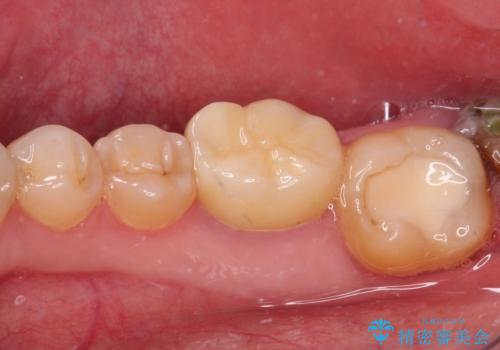

- 左右下顎の奥歯に違和感を感じるとのことで来院された患者様です。

最近ものが挟まりやすくなったり、冷たいものがしみるようになったりと言った症状があり、診査したところ、歯質の欠損や不適修復物などが認められました。

精度の高いセラミックインレーによる修復治療が第一選択となりますが、一方の歯は元々修復物が大きく、咬合力の強い方であったので、セラミッククラウンによる補綴治療を行うこととしました。